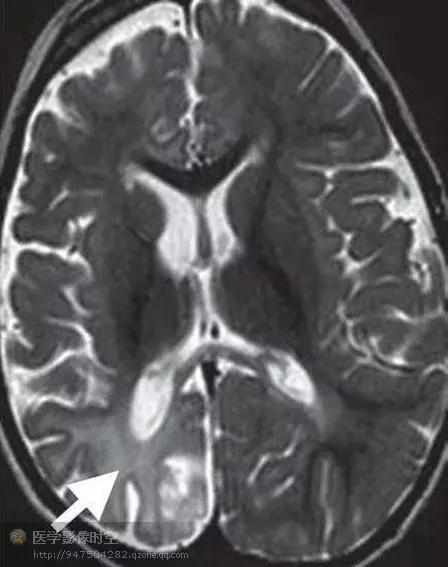

结节硬化病人伴发难治性癫痫的病人常常具有多发结节。因此准确识别引起癫痫活动的结节非常重要。单靠磁共振成像成像难以完成该工作。联合应用磁共振成像和脑电图数据,进行相关分析,有时候可以找到病变位置。最近,MR-PET融合图像和磁源成像能够提供结节硬化相关性癫痫灶的定位。发作间期MR-PET融合图像上具有癫痫活动的结节硬化病变显示为低代谢区,范围大于相关的磁共振成像信号异常区(例如年龄大于6月儿童的T2WI高信号区)(图7)

图7 继发于左侧颞叶前极的结节硬化结节的难治性癫痫

图7a横断FLAIR图像图像显示多发的皮层和皮层下结节(箭头)

图7b横断发作间期MR-PET融合图像显示左侧颞极大的低代谢区(箭)。术中脑皮层电图显示弥漫性代谢减低区,提示癫痫灶。 发作间期磁源成像可以通过配准癫痫样放电与磁共振成像解剖图像方法显示癫痫性结节。

图8 继发于右顶叶后内面的结节硬化结节的难治性癫痫。

图8a横断FLAIR图像图像显示多发的皮层和皮层下结节(箭)

图8b横断发作间期MR-PET图像显示多发的低代谢区,与结节硬化结节吻合。没有发现与FLAIR图像上局部结节不成比例的低代谢区。

图8c横断发作间期磁源成像显示继发于右后顶叶结节的癫痫样活动。